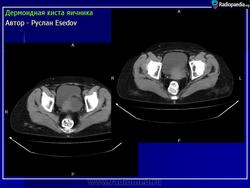

Дермоидная киста.